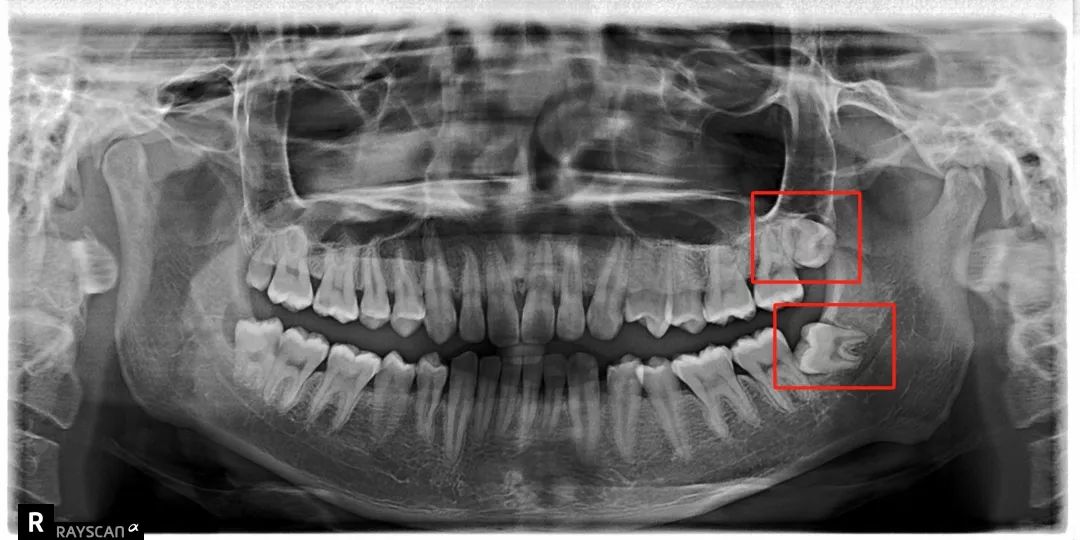

把整副牙齿挤歪:

比方说像树根一样长出很多「根」

扎根在骨头里,死死抓住

还有一部分智齿长期发炎

可能会跟我们的骨头黏连